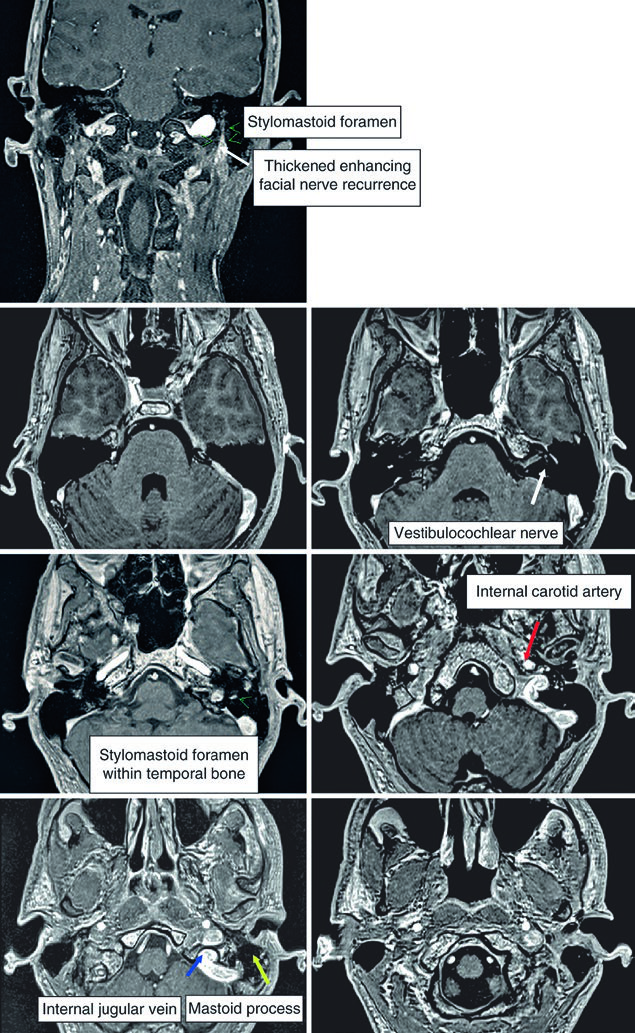

For parotid tumors, the facial nerve, glossopharyngeal nerve, and V3 branch of the trigeminal nerve must be included. In cases with extensive spread, coverage may need to extend to Meckel’s cave. The intratemporal course of the facial nerve deserves particular attention — it runs through the facial canal from the internal auditory canal to the stylomastoid foramen. When there is direct involvement or when the histology is adenoid cystic carcinoma, inclusion of this pathway is mandatory.

T1-weighted images excel at delineating tumor margins. When fat-saturated, contrast-enhanced T1-weighted sequences are added, perineural spread, bone invasion, and meningeal infiltration become far more conspicuous. In clinical practice, fusing the simulation CT with diagnostic MRI is strongly recommended — it combines the geometric accuracy of CT with the contrast resolution of MRI, yielding a more confident delineation.

The fusion workflow between simulation CT and diagnostic MRI deserves emphasis as an essential step in current practice. CT provides the geometric reference for dose calculation, while MRI delineates the tumor-normal tissue interface with greater precision — particularly in deep-lobe parotid tumors, where the distinction between glandular parenchyma and the pterygoid muscles can be subtle. Whenever possible, MRI should include axial and coronal fat-saturated gadolinium-enhanced sequences, as these reveal infiltration patterns that may go undetected on conventional CT.